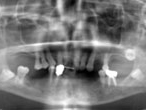

Case.01 骨造成インプラント治療症例

初診時

上下顎に数本の歯が残っていますが咬合支持がほとんどないために満足に食事もできない状態でした。また、下顎前歯部から臼歯部にかけて骨吸収が進行しており、上顎臼歯部にインプラント治療を行うためには骨造成が必要な状態です。

レントゲン